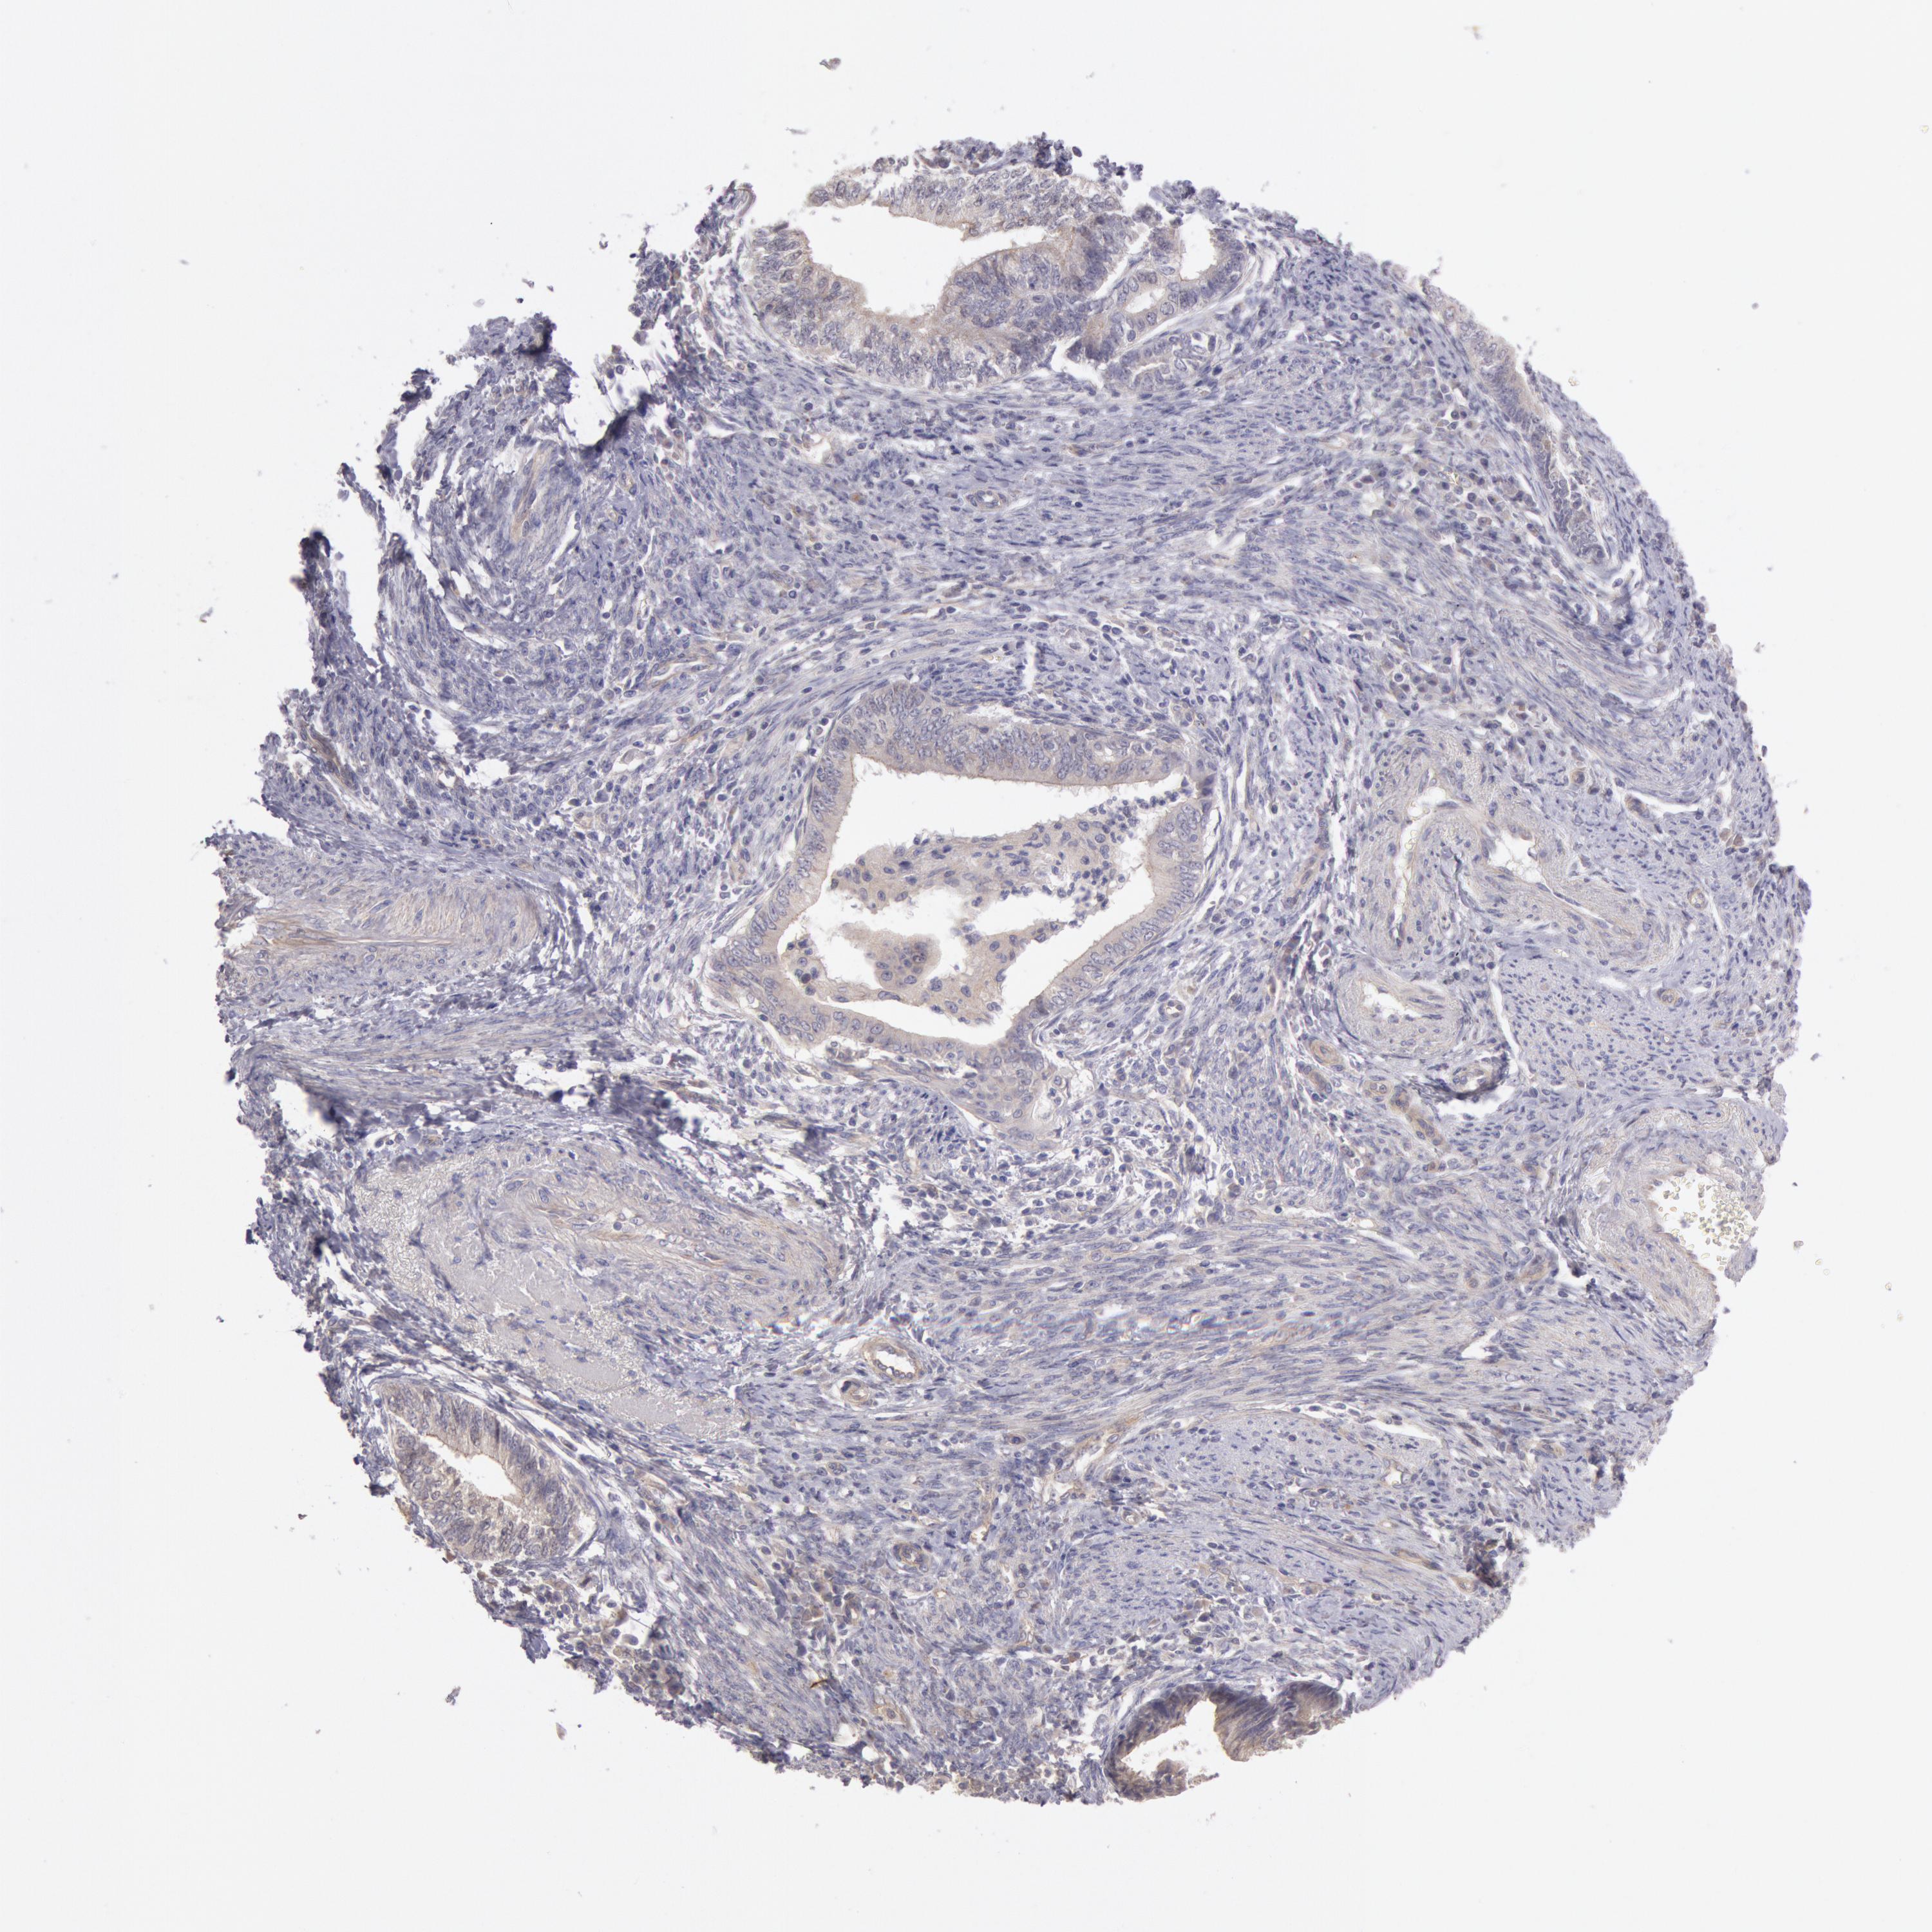

ENDOMETRIAL CANCER - Protein expressioni

A mouse-over function shows sample information and annotation data. Click on an image to view it in a full screen mode. Samples can be filtered based on level of antibody staining by selecting one or several of the following categories: high, medium, low and not detected. The assay and annotation is described here.

Note that samples used for immunohistochemistry by the Human Protein Atlas do not correspond to samples in the TCGA dataset.

Antibody stainingi

Antibody staining in the annotated cell types in the current human tissue is reported as not detected, low, medium, or high, based on conventional immunohistochemistry profiling in selected tissues. This score is based on the combination of the staining intensity and fraction of stained cells.

Each image is clickable and will lead to virtual microscopy that enables deeper exploration of all samples and also displays staining intensity scores, fraction scores and subcellular localization as well as patient and tissue information for each sample.

Antibody HPA001196

Staining

High

Medium

Low

Not detected

Intensity

Strong

Moderate

Weak

Negative

Quantity

>75%

75%-25%

<25%

None

Location

Nuclear

Cytoplasmic/membranous

Cytoplasmic/membranous,nuclear

Adenocarcinoma, NOS